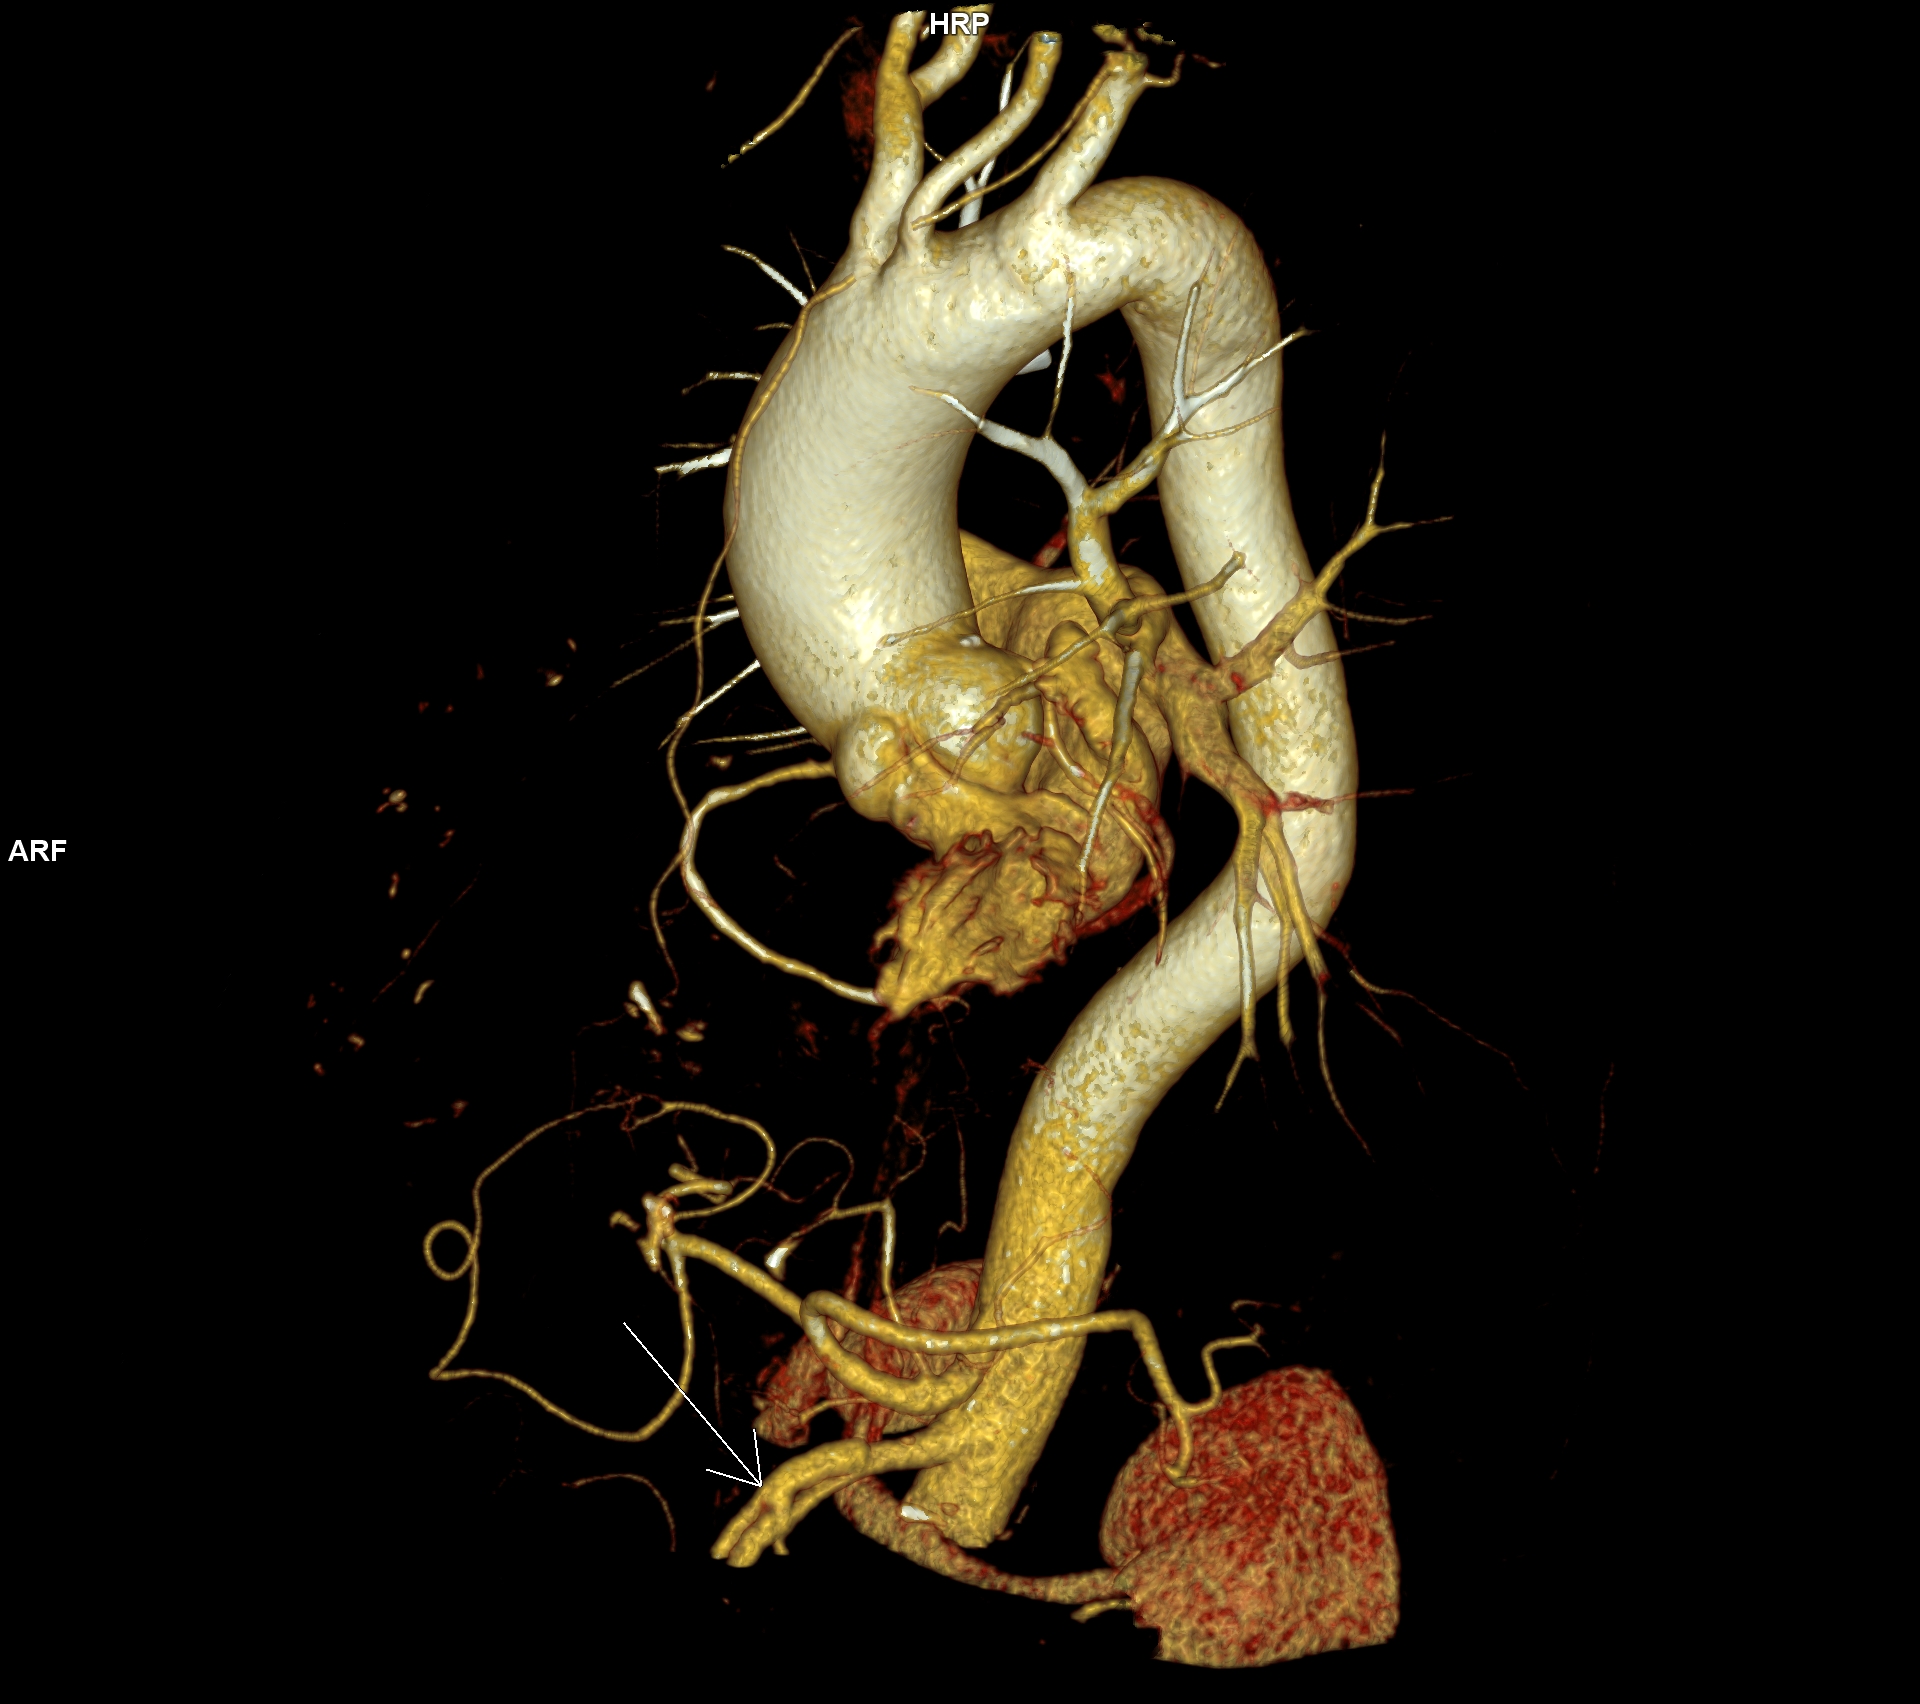

Figura 3: reconstrucție VRT din achiziție angioCT torace și abdomen superior cu evidențierea disecției de arteră mezenterică superioară cu ambele lumene circulante

Discuţie caz nr 128: Valva aortică este bicuspidă prin coaptarea cuspei pentru sinusul Valsalva drept și cuspei pentru sinusul non-coronarian, la nivelul cooptării fiind prezenta o calcificare. Secundar valvei aortice bicuspide se remarca creștere de calibru a aortei ascendente, acesta fiind și motivul îndrumării pacientului la examinare CT de aortă toracică – examinare care ar trebui sa fie efectuată obligatoriu cu sincronizare ECG. Întâmplător, la limita inferioară a câmpului de scanare, la nivelul arterei mezenterice superioare se evidențiază un fald de disecție cu ambele lumene circulante.